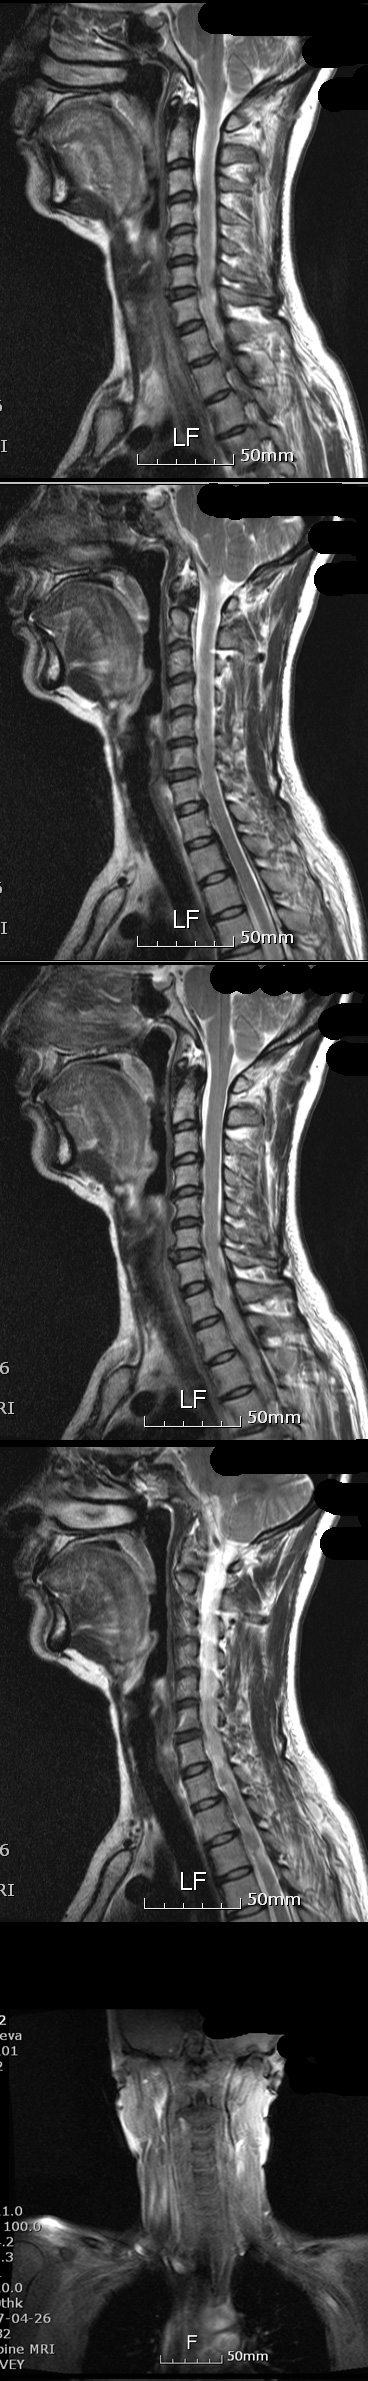

5143 10 ش , װ ; ۼ ȿ* Ȩ/α ۼ 2010-07-14 20:52:53 ̸ tea***@hanmail.net 211.200.116.189 ȸ 7801 Ű 157 51 54 ˰Ե ͳ ī䳪 α õ ڸǥغ ǥغ ϱ ȣϽ 1C.Ż, 1C.ڵ, 1C.ڵӸ 1C. ٿ, 1C.ٺҸ, 1C.ٰ 1C. ٸǷ 1C.ں 1C.ڱ ֺ 3C. ڱ() 3C.ھ 5C.ھ 6C.ڸ 6C. ھ Ḳ 6C.ڻ 7C.Ȳġ 1T.ڼո 1T.ڼհ ü ̳ 1T.Ȳġ 5T.ڹ߿ 10T.ٸǷ 1L. 5L.ڹ߸̳ 5L.ڹ߰ ̳ ȭŸ̳ ڸǥغ ǥغ Ը Ͽ , Ḳ ġ Ǵ , , Ǵ ġ Ҹ ġ ߰ ġ Ǵ ġ ڰ, 鹫ȣ, ߵ ڰ Ǵ ġ Ƿ ġ Ǵ ġ ڸǥغ ǥغ ϰ ߴ ġẴ ߺ:10 :1.(). ó - ʾ 㿡 . ٴ÷ ų Ȥ ϱϰ Ǵ õ ̶ . ڰ . 2.- ְ . κ θ κ ó ϰ (Ư Ÿ 鼭 ) 3.- ó 4.Ӹ- Ӹ Ӹ (Ÿ̷ε ) 5.߸- η 6.Ǹ̳ ġẴ:1.**( ȳ) 2.**(MRI,CT-ũ ƴ϶ ) 3.**Ƿ((MRI,-ӻ غڰ..) 4.**뺴(MRI-ũ ƴ϶ ) 5.**뺴(ȣ⳻,Űܰ,ŰŰ: ġ) 6.**ġ(ΰ -ǰߴ ġ9 Ƴ ٽ 7.ü(1ġ)-ä,ô߱,ʻ,ħ.. *纴 ũ ƴ϶մϴ. Ư ** ϳ ܿ ٳϴ. ϴ ϵ 䰡 1 Ǿ.. ͳ ˻ α ũ Ƽ Խϴ. Զ ½ ߿ϴ O ٴϱ 10.. Ե ִϴ. ɷ ο Ǿ ڽϴ. ---------------------- 4 ҰԴϴ. 10 ش , װ ; no 5152 date 2010-07-14 20:52:53 hits 213 name ȿ* (team**@hanmail.net) IP: 211.200.116.189 10 ش .. װ ;. 㸸 Ǹ ãƿ Ϸ翡 1~2ð ڱġ 10̾. ٸ ΰ (ӹ) ֺ ̸ , ٴ÷ , õ ʹ. δ ûϱ ؼ ִٰ Ա ǵ帮 ҽġ ߴ. ȹٷ ϴ ڼ (ȹٷ ߸ ̻ ٱ ) ڴٺ ô ֹ ;, ̸ ãƿ Ϳ ߸ ڴٰ Ͼ ⸦ 10. ־ Ӹ ο Ǹ ôȴ. ħ Ͼ 뽺 ڿ ¿ ٸ ̻ ٱ ٸ ÷ ݰ ɾҴ. ð ⸦ Ż عٴڿ ݰ ߴ. õİ ˷ ް 鼭 ãƴٴϴ к 5 ܿ ΰ ü ġḦ Ҵ. MRI, CT, ˻縦 Ȯ ߴ. ε ϰ ε ʾ ϴ ϵ ΰ ĥ ģ 쿬 ͳ ˻ ǥغ ˰ Ǿ. ڸ Է ٲ㰡 Ը 17. Ե 3 Ǵٺ ġ μ Ӵ ġ ۿ . Ẹ ϸ ǰ϶ ̾. ȸ絵 ֱ ;. Ը ް 4 ξ ð Ű . Ҿ ִ Ͽ. 1. 1) -ӹ ֺ 2) -, , () 3) Ӹ- Ӹ 4) ΰ 5) 6) Ȳġ ո 7) հ-ڴٰ ǵ帮 ¦ 8) ٸ-ڿ ɾƼ ٸ ̻ ٱ κ (ȹٷ ..) 9) ߸-ȹٷ 10) Ǹ ( 3~4ȸ) 11) ( ó) 12) -ħ Ͼ ǥغ ȸ ǥغ ϱ ȣߴ Ż, , Ӹ, , Ҹ, , Ƿ, ֺ , (), , , , Ḳ , , Ȳġ, ո , հ ü ̳ , ߿, (ε巯) , ߸̳ , ߰ ̳ ȭŸ̳ 2. ġ 1) A-MRI 2) S-MRI, CT( ũ ƴ϶ .) 3) S1-MRI, ˻(ӻ غڰ..) 4) I-ȣ , ̺İ, Ű Ű( ġ) 5) J-MRI( ũ ƴϴ ׳ .) 6) Yġ-ΰ (ǰ ġ 9 Ƴ ٽ , 2) 7) ü -ô , ä, ħ, ʻ(ġ ʹ 뽺) 3. ǥغ ϱ 7/10() :3, Ӹ:3, ħ ħ´ ܿ ̺ 3, е 1 () * ް ´ ȸԲ ȭ ּż ֽ. * ̿ ϰ 2 ð 귶? ó . * ȸԲ ? ִ ̴. * 10 ħ . ̷ !! * ? ȸ ް ħ ̴. * ֿ Ʈ е带 µ κа Ӹ κ ϴ ̴. Ӹ κ Ͽ ̸ ϴ ũ Ӹ ƴ϶ 㸮 ϱ ٸ ϵ Ͽ شٰ Ѵ. Ÿ ִ Ȯ ġ پų Ѵٴ ε Ȯ ġ ϸ Ӹ е带 ְ . Ͻôµ ȸԲ ϴ ŭ е带 ־ 鼭 Ͽ پ Ȯ ־. ̷ 1ð̻ ȭ ٿ űϿ ߸Ǹ ִٰ Ѵ. * Ϸ ִ ٽ (߿ ˰ ǰ ߰ ٽ Ÿ ) * ġ Ȯϰ ġ ȿ ص ʴ´ٴ ǥظƮ û. () * ʴ 㸮 Ǹ . * ϳ ġᰡ ɱ . Ѵ̶ ϰ ڰ ߴ. ٽ ο Ͽ ˰ ٴ ħ ̶. 7/11() :11, Ӹ:2, ħ ǻ ٽ () * 9 ʴ 鼭 ٽ * ̺ ܿ ̺ ٽ Լ * ٽ ٽ * 1ð 2ȸ ( Դٰ ) () * ߴ ٿ (ȿ .) * 5ð ̹ 7/12() :11, Ӹ:2 () * ǥظƮ , 748 * () * 12 ڸ . * 2~210- Դٰ ( 1 3~4ȸ Ͼ ġ) * 210- ɰ ۵Ǵ ܴ ڸ ε巯ó * ߵ, ߸, , Ƹ , , յ, ո, Ȳġ( Ÿ) * ܿ , 㸮, , , Ʒ, . * 4~6ñ ٽ ( ) 7/13(ȭ) :6, Ӹ:6 () * 930а ȸ ٽ (-9 ߿ ־ٰ ) * MRI CD ã * Ϸ ȸԲ ֽ ڼ (պ ) * Ÿ պ 4ð ȿ ڼ. * 330а ٽ * 6~8ñ ( ) () * 11ÿ ʰ ڸ * ʾ 2ð ô̴ ħ 6ñ 7/14() :6 , Ӹ:6 () * 9 45 ȸ ٽ * ణ * , , 㸮 ó ǥغ 4 ǥظƮ 2 ڰ Ͼ 5°. â ۿ Ÿ Ҹ ٽŰ( ħ Ͼ ) å . պ ô!!( ȸԲ ֽ ) ջ ϴ ;ɾҴ ħ Ȱ ־. 10 . Թ翣 ɾ ÿ߸ ä ; Ʒ Ͽ кɾ ư Ͼ ģ ä Ǿ. λ ٽ ϱ? üµ ȸؾ ϰ ǰ ãƾ ϰ ڰ Ͼ ħ. ̰ε ູϰ ູϴ!! ٽ ȸ ǥغԡ в ϸ鼭 ȣ ǰ ı . ֿ ȿ*ø. * : ɴϴ.. ٴ Ѵ 鿩˾ 15.. մϴ..ȭ ^^ 2010-07-14 22:23:31 * : !!! ذ ˴ϴ..ڲٸ þ߰ ϴ.. 2010-07-14 22:39:23 ȿ* : ϴ!! 漮Ե ~~ ȱ!! 2010-07-15 08:13:56 Ȩ : Ͻ *Դϴ. ̵ֹ : 20100709095247team58] Ʈ ù ϼ̽ϴ 2010-07-15 22:28:52 Ȩ : ۼϽ 漮Ե ϼ̰ Ŀ ϴ ִ Դϴ. 2010-07-16 08:19:15 Ȩ : 漮 κ Ӵ ǥظƮ ߰ ϼ̽ϴ. ȸԲ ϼ̰ ° ص帱 Դϴ. 2010-07-16 08:20:44 Ȩ,,,,, : ı մϴ 20100709095247team58] * ֹ ֹϽ 2010-07-16 11:26:38 Ȩ,, : 7094632590816 2010-07-16 16:08:5 : ذϴ ḸǸ ̷ ״±߽ϴ 1 99%䱹κȭñȿ òϼ 2010-07-20 09:41:49 ȿ* : ϴ! ϴ 2010-07-20 10:25:22 Ȩ : ֽ 漮Ե Ŀ 1 Ѱ ߴ ϸ ֽϴ. ġ ϼ. 2010-07-20 12:15:14 Ȩ : κ ȸ ϼż ȿ Ȯ ȿ Ÿϴ. 輱 迵ռԵ ȸԿ ϸ Ȥ ϴ 찡 ־ ġ µ ð ɸ Ѵϴ. 2010-07-20 12:17:12 * : ..¥..ϳ.. ̷ ߿ ... .. ʱ.. ̿ ˰ Ǿ..ʹ ູؿ~! ƺ ҸӴ .. 2010-07-23 10:17:46 ȿ* : ! ٰ ִ ϴ. ֺ ݽŹϰ ִ .. Բ ̴ٴ ϵ帳ϴ!! 2010-07-23 11:09:21 -------------------------------------------------------------------------------------------------------------------------------------------- ٰ ִ ϱ? no 5180 date 2010-07-17 13:11:58 hits 187 name ȿ* (team**@hanmail.net) IP: 211.200.116.189 ǥغ 귶. â ۿ ߰ ̸ Ϸ .. ۾˼۾ ִ ٶ 10 Ǹ Ҵ ð ҷ. Ͼ ϱ? ٰ ִ ϱ? ʴ. ϴ ̷ ɾ ٳణ ̹ ó Ӵ. ջ꿣 ܿ ҳ ø ä ° ְ ߷ ͱ ö ٱ Ǫ ʿŸ. ñ ̿ г . ΰ ȭӰ ΰ ູϰ ΰ Ӵ. 28 ڸ Ƹ Ǫ ̴.(ȥ) ̷ ä ð, ؾ߰ڴ. ʰ ູ Ǫ Ű Ű ڳ.. Կ װ ִ ٶ ڸ ı鿡 Ѵ. ϴ! ϴ! մϴ! ֿ ȿ* ø * : Ʒ..幮 ̴ּ ̽ñ~ ...ۼؾ Ͻó.. 뿡 ̴ٴ.. .. .. ʿ䰡 ° ƿ..ȣ~ ູؿ~ 2010-07-23 10:19:26 ȿ* : Բ ּż ϴ! Ϸ ٱ Ϸ ٻµ ´ϴ. ٸ ڼ ϸ鼭 Ͽ Ѵٴ ȸ ʰ ÷ ϰ ֽϴ. 忡 2010-07-23 11:16:20 ȿ* : Բ ּż ϴ! Ϸ ٱ Ϸ ٻµ ´ϴ. ٸ ڼ ϸ鼭 Ͽ Ѵٴ ȸ ʰ ÷ ϰ ֽϴ. 忡 2010-07-23 11:16:20 ȿ* : ٰ, ĿǼ, .. ʾ ~~ 2010-07-23 11:20:43 |